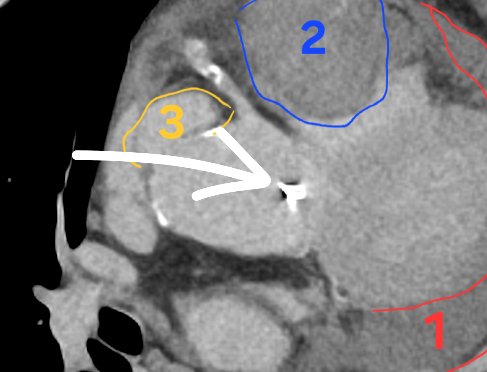

En 3 : une image d'addition en regard de l'aorte ascendante. Ça n'est PAS normal. C'est très dur à détecter quand on n'a pas l'habitude ou qu'on ne le recherche pas... C'est ça la cause de l'hémopericarde. Regardez la vidéo pour bien voir comment on repère cette anomalie

Bonus : la cause est visible ici ! En limite de champ on voit un bout de bioprothèse aortique. Le patient avait déjà été opéré... Il y a probablement eu endocardite (d'où la fièvre...) et rupture aortique sur ancien trajet de CEC...

En 2 : un hématome intra péricardique. Ça c'est plus dur à détecter et déterminer, regardez la vidéo pour bien comprendre. Ça nous fait affirmer que 1 est forcément pathologique, et doit nous faire absolument rechercher la cause.